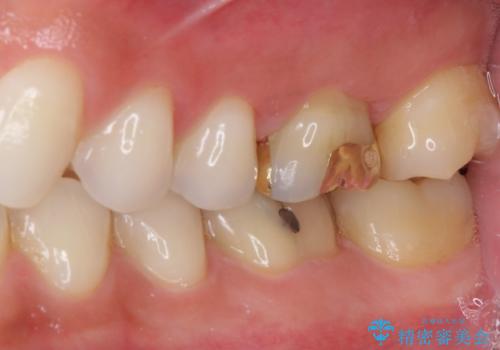

ゴールドインレーは銀歯のインレーやセラミックインレーと比べ、「技工操作の精度が高く、適合が著しく良い」というメリットがあります。特に上の奥歯は歯科医師の操作が行いにくいため、「適合の良さ」は再治療のリスクを防ぐ上でとても重要な要素となります。

上の奥歯は金属色が見えることもないため、審美的な問題は全くありません。

咬み心地はとても良好で、全く違和感がなく、患者様には大変満足していただきました。